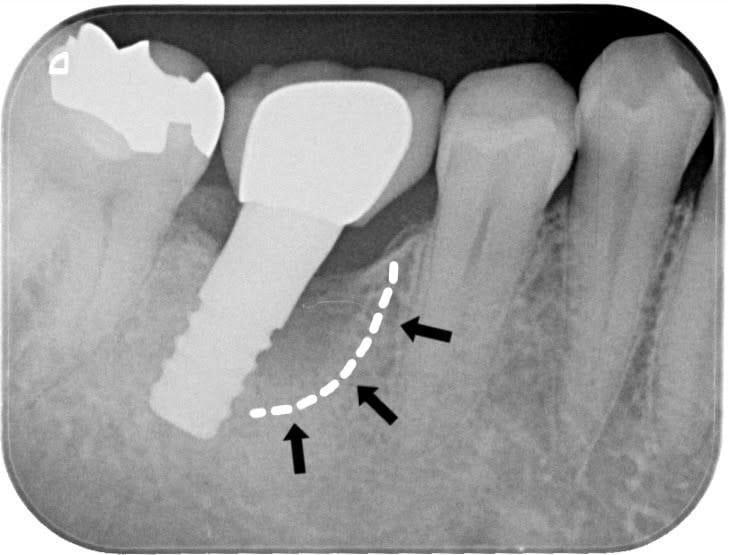

前医でインプラントの埋入角度が悪く、インプラント周囲炎になってしまった患者様の症例です。

インプラントが虫歯になることはありませんが、インプラント周囲炎というインプラントの歯周病にはなります。

インプラント周囲炎の主な原因は汚れ(菌)と力です。このように斜めに埋入されているインプラントは、真っ直ぐ埋入されているものに比べて汚れも溜まりやすく、噛む力も斜めにかかってしまうため、インプラント周囲炎になるリスクが大幅に高くなります。

この患者様は内側の骨が大幅に溶けてしまっていたので、前のインプラントを撤去して、骨を再生させると同時にインプラントを正しい位置と角度で埋入し直しました。溶けてしまっていた骨が治っていることもレントゲンでご確認いただけるかと思います。

インプラントは「どこの位置にどのような角度で入れるか」によって、一生使い続けられるかどうかの期待値が大きく異なります。値段だけを基準にクリニックを決めるのではなく、信用できる歯医医師と治療を進めることをお勧めします。